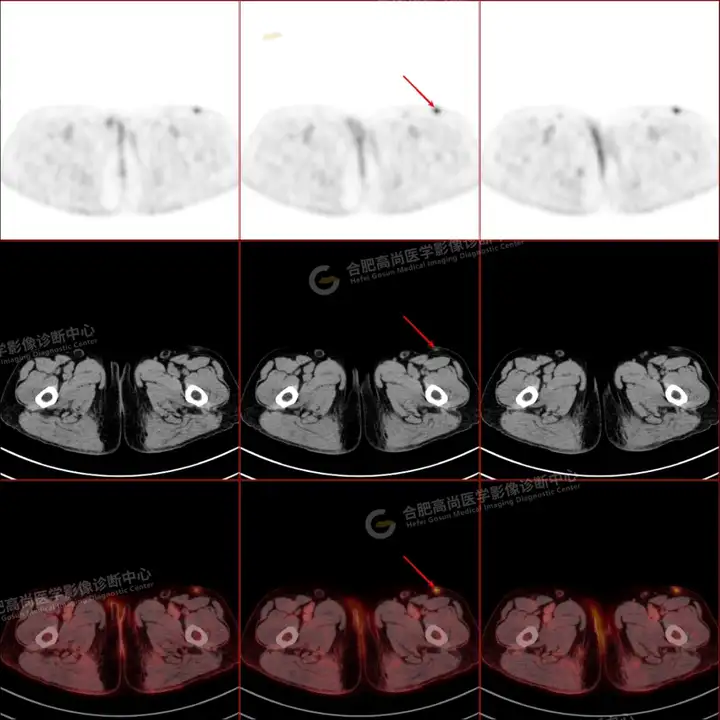

PETCT检查所示:图1、3-17全身多处(双上臂、胸背部、左侧乳腺、左侧腰部、腹壁、双侧臀部及双侧大腿)皮肤下结节及肿块样软组织密度灶,FDG代谢不同程度增高,双侧颈部、左侧锁骨区、纵隔内(1区)及双侧腋窝多发肿大淋巴结,FDG代谢明显增高,符合皮肤来源淋巴瘤。